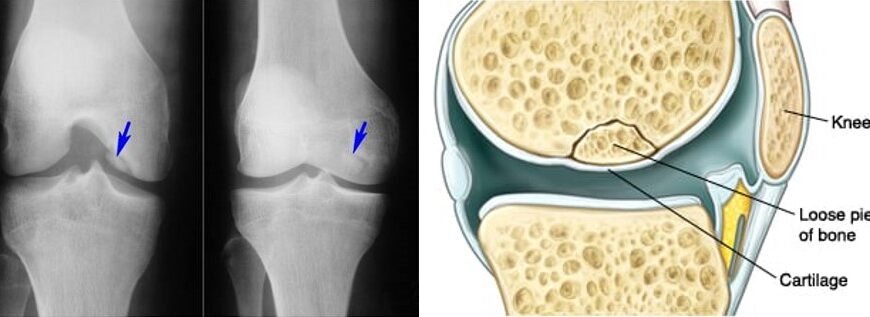

Почнемо з того, що хвороба Кеніга, більш відома науково як остеохондрит розсійка, являє собою стан, за якого частина кістки вкритої хрящем відшаровується — прямо всередині суглоба. Зазвичай ця біда коїться у коліні. Коли все отак тріщить, що може бути гірше?

І що ж у кінцевому рахунку? Без правильного лікування частинка кістки може повністю відірватися — приводячи до хронічного болю чи, навіть, втрати функціональності.

- Рентген: заморозити кадр, щоб побачити те, що приховано.

- МРТ: глибокий скан мозку сутності кістки і хряща.